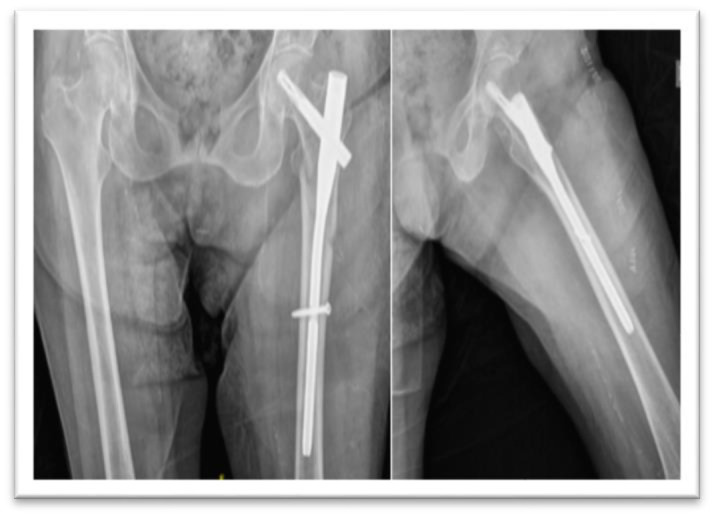

Objectives: Treatment of subtrochanteric fractures of the proximal femur may be challenging due to their anatomical and biomechanical features. Intramedullary nails are the most frequently used devices, although there is no consensus concerning their optimal length. The aim of this study is to compare the functional and radiological outcomes of the fragility subtrochanteric fractures treated with short versus long cephalomedullary nails.

Methods: A retrospective cohort study was performed including all over-65-year-old patients that underwent surgery with a cephalomedullary nail between January 2013 to December 2020 due to a subtrochanteric fracture. The primary outcome was the presence of mechanical complications (cut out, cut in, varus consolidation, nonunion and nail breakage). Accuracy of the reduction, distance from the fracture line to most proximal distal screw, operative time and Palmer Mobility score were also analyzed.

Results: Ninety-five patients were included. There were not significant differences in complication rate, Parker mobility score nor quality of reduction between both cohorts. Patients with a good radiological reduction presented no complications, those with an acceptable reduction presented a complication rate of 35.5% and it raised to 53.3% in poorly reduced ones (P=0.002). The complication rate was higher in the <5cm distance group (58.33%) than in the >5cm distance group (22.64%) (P=0.014).

Conclusion: Anatomical reduction may be the key factor in the management of subtrochanteric fractures, in order to avoid complications. The chosen device working length should also be taken into account to treat these challenging injuries.